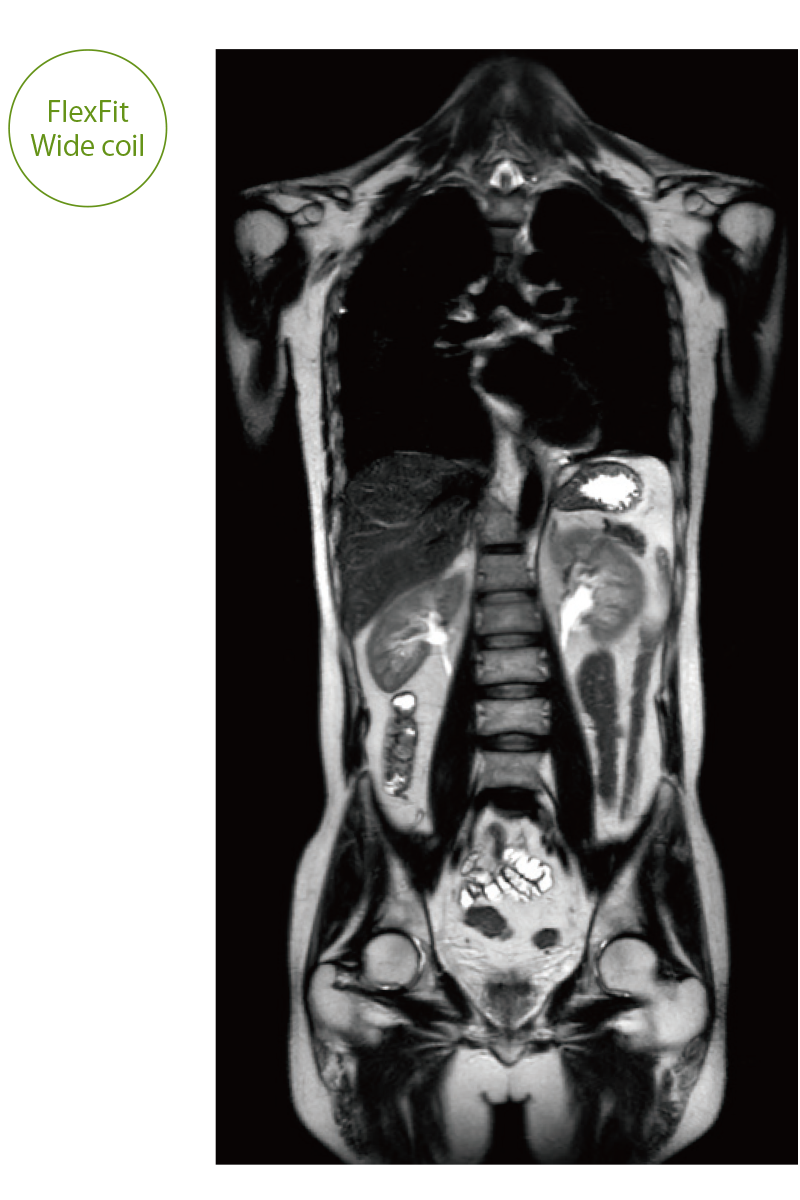

IP-RAPID×DLR PlusはVolumeScanやRadialScan、HalfScanといった基本撮像に加え、MultiContrastScanのFatSepやDWIなど多くの撮像法でお使いいただけます。広範囲DWIやWhole Spine撮像など時間のかかるWide Scanにも併用でき、多くの部位で従来よりも詳細な情報を得ることができます。

ECHELON Synergy ZeroHeliumはスライド装着でOneアクションセッティング可能なフレキシブル頭頸部用コイルや、撮りたい場所をフレキシブルにワイドにカバーできるFlexコイルを備え、部位に応じて柔軟に対応できます。